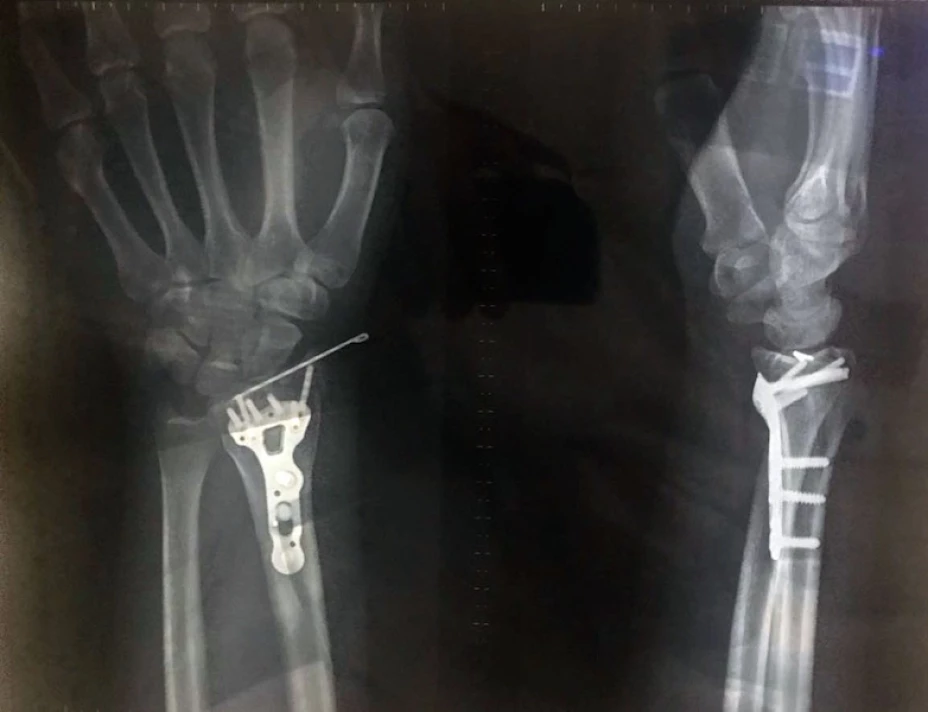

Enfatizó que evitar las fracturas es de gran importancia, pues las principales complicaciones asociadas son dolor y limitación, inmovilidad prolongada, ulceras, infecciones, pérdida de la autonomía y depresión, además de gastos para la familia.